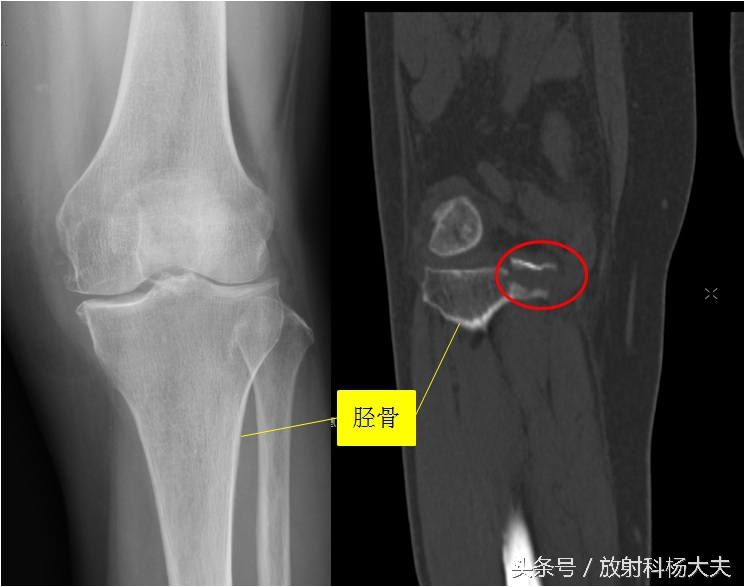

比如下图的X线片,发生在胫骨平台的骨折,很难发现。但做了CT,就比较容易了,如图中的红圈。

关键的一步是谁想到建议做CT。有的时候是有经验的骨科大夫,根据体检,高度可疑胫骨平台骨折,但X线却没发现异常,此时会建议病人做CT或者MRI。有的时候是有经验的放射科大夫,读片的时候总觉得胫骨平台有的地方不对劲,再去查查体,怀疑胫骨平台骨折,会建议做CT或MRI。